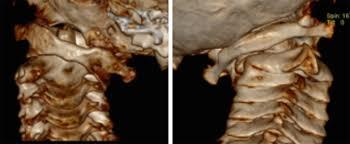

检查显示严重的寰枢椎固定脱位,脊髓也受到压迫。

牵引复位,螺钉固定,植骨融合,效果还是非常好。我们的手术安全并且出血极少。